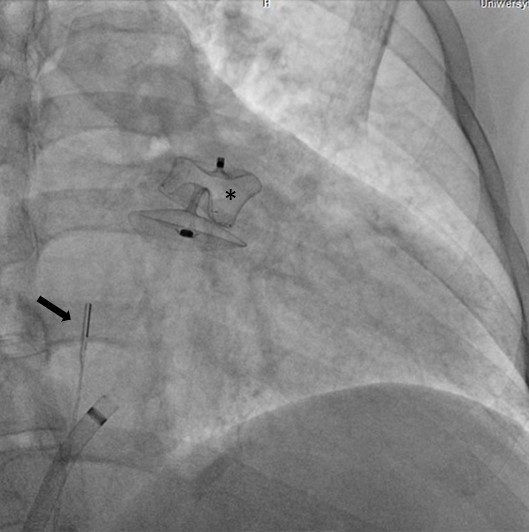

Specjaliści z Pracowni Kardiologii Inwazyjnej I Kliniki Kardiologii UCK przeprowadzili 3 zabiegi zamknięcia uszka lewego przedsionka (ang. LAAO – left atrial appendage occlusion) z wykorzystaniem systemu echokardiografii wewnątrzsercowej (ang. ICE – intracardiac echocardiography).

Zabiegi LAAO wykonuje się u pacjentów z migotaniem przedsionków i wysokim ryzykiem udaru niedokrwiennego mózgu, którzy nie mogą stosować leczenia przeciwzakrzepowego z powodu wysokiego ryzyka powikłań krwotocznych. Rutynowo przeprowadzane są one pod kontrolą echokardiografii przezprzełykowej (ang. TEE – transoesophageal echocardiography).

– U części pacjentów kwalifikowanych do LAAO ryzyko związane z wykorzystaniem obrazowania metodą TEE jest zbyt wysokie ze względu na poważne zmiany chorobowe przełyku. To dotychczas uniemożliwiało wykonanie zabiegu. Obrazowanie metodą ICE pozwala na bezpieczne wykonanie zabiegu zamknięcia uszka lewego przedsionka również w tej grupie chorych, ponieważ specjalną sondę ultrasonograficzną wprowadza się nie do przełyku, lecz przez układ żylny pacjenta, bezpośrednio do jam serca – mówi dr Dariusz Ciećwierz, koordynator Pracowni Kardiologii Inwazyjnej I Kliniki Kardiologii UCK z I Katedry i Kliniki Kardiologii GUMed. – Dodatkową korzyścią tego rozwiązania jest większy komfort pacjenta w trakcie zabiegu, dzięki czemu można uniknąć sedacji czy znieczulenia ogólnego.

W ramach przygotowania do wprowadzenia metody do praktyki klinicznej w UCK, zespół zabiegowy miał możliwość przetrenowania jej zastosowania na zaawansowanym symulatorze w Centrum Symulacji Sercowo-Naczyniowej GUMed. Zabiegi wykonano u dwóch pacjentów z zaawansowanymi żylakami przełyku z powodu marskości wątroby oraz u pacjentki z wrodzoną naczyniakowatością krwotoczną (choroba Rendu-Oslera-Webera). Nadzór merytoryczny w trakcie pierwszych przeprowadzonych zabiegów zapewnił dr hab. Witold Streb, kardiolog ze Śląskiego Centrum Chorób Serca w Zabrzu.